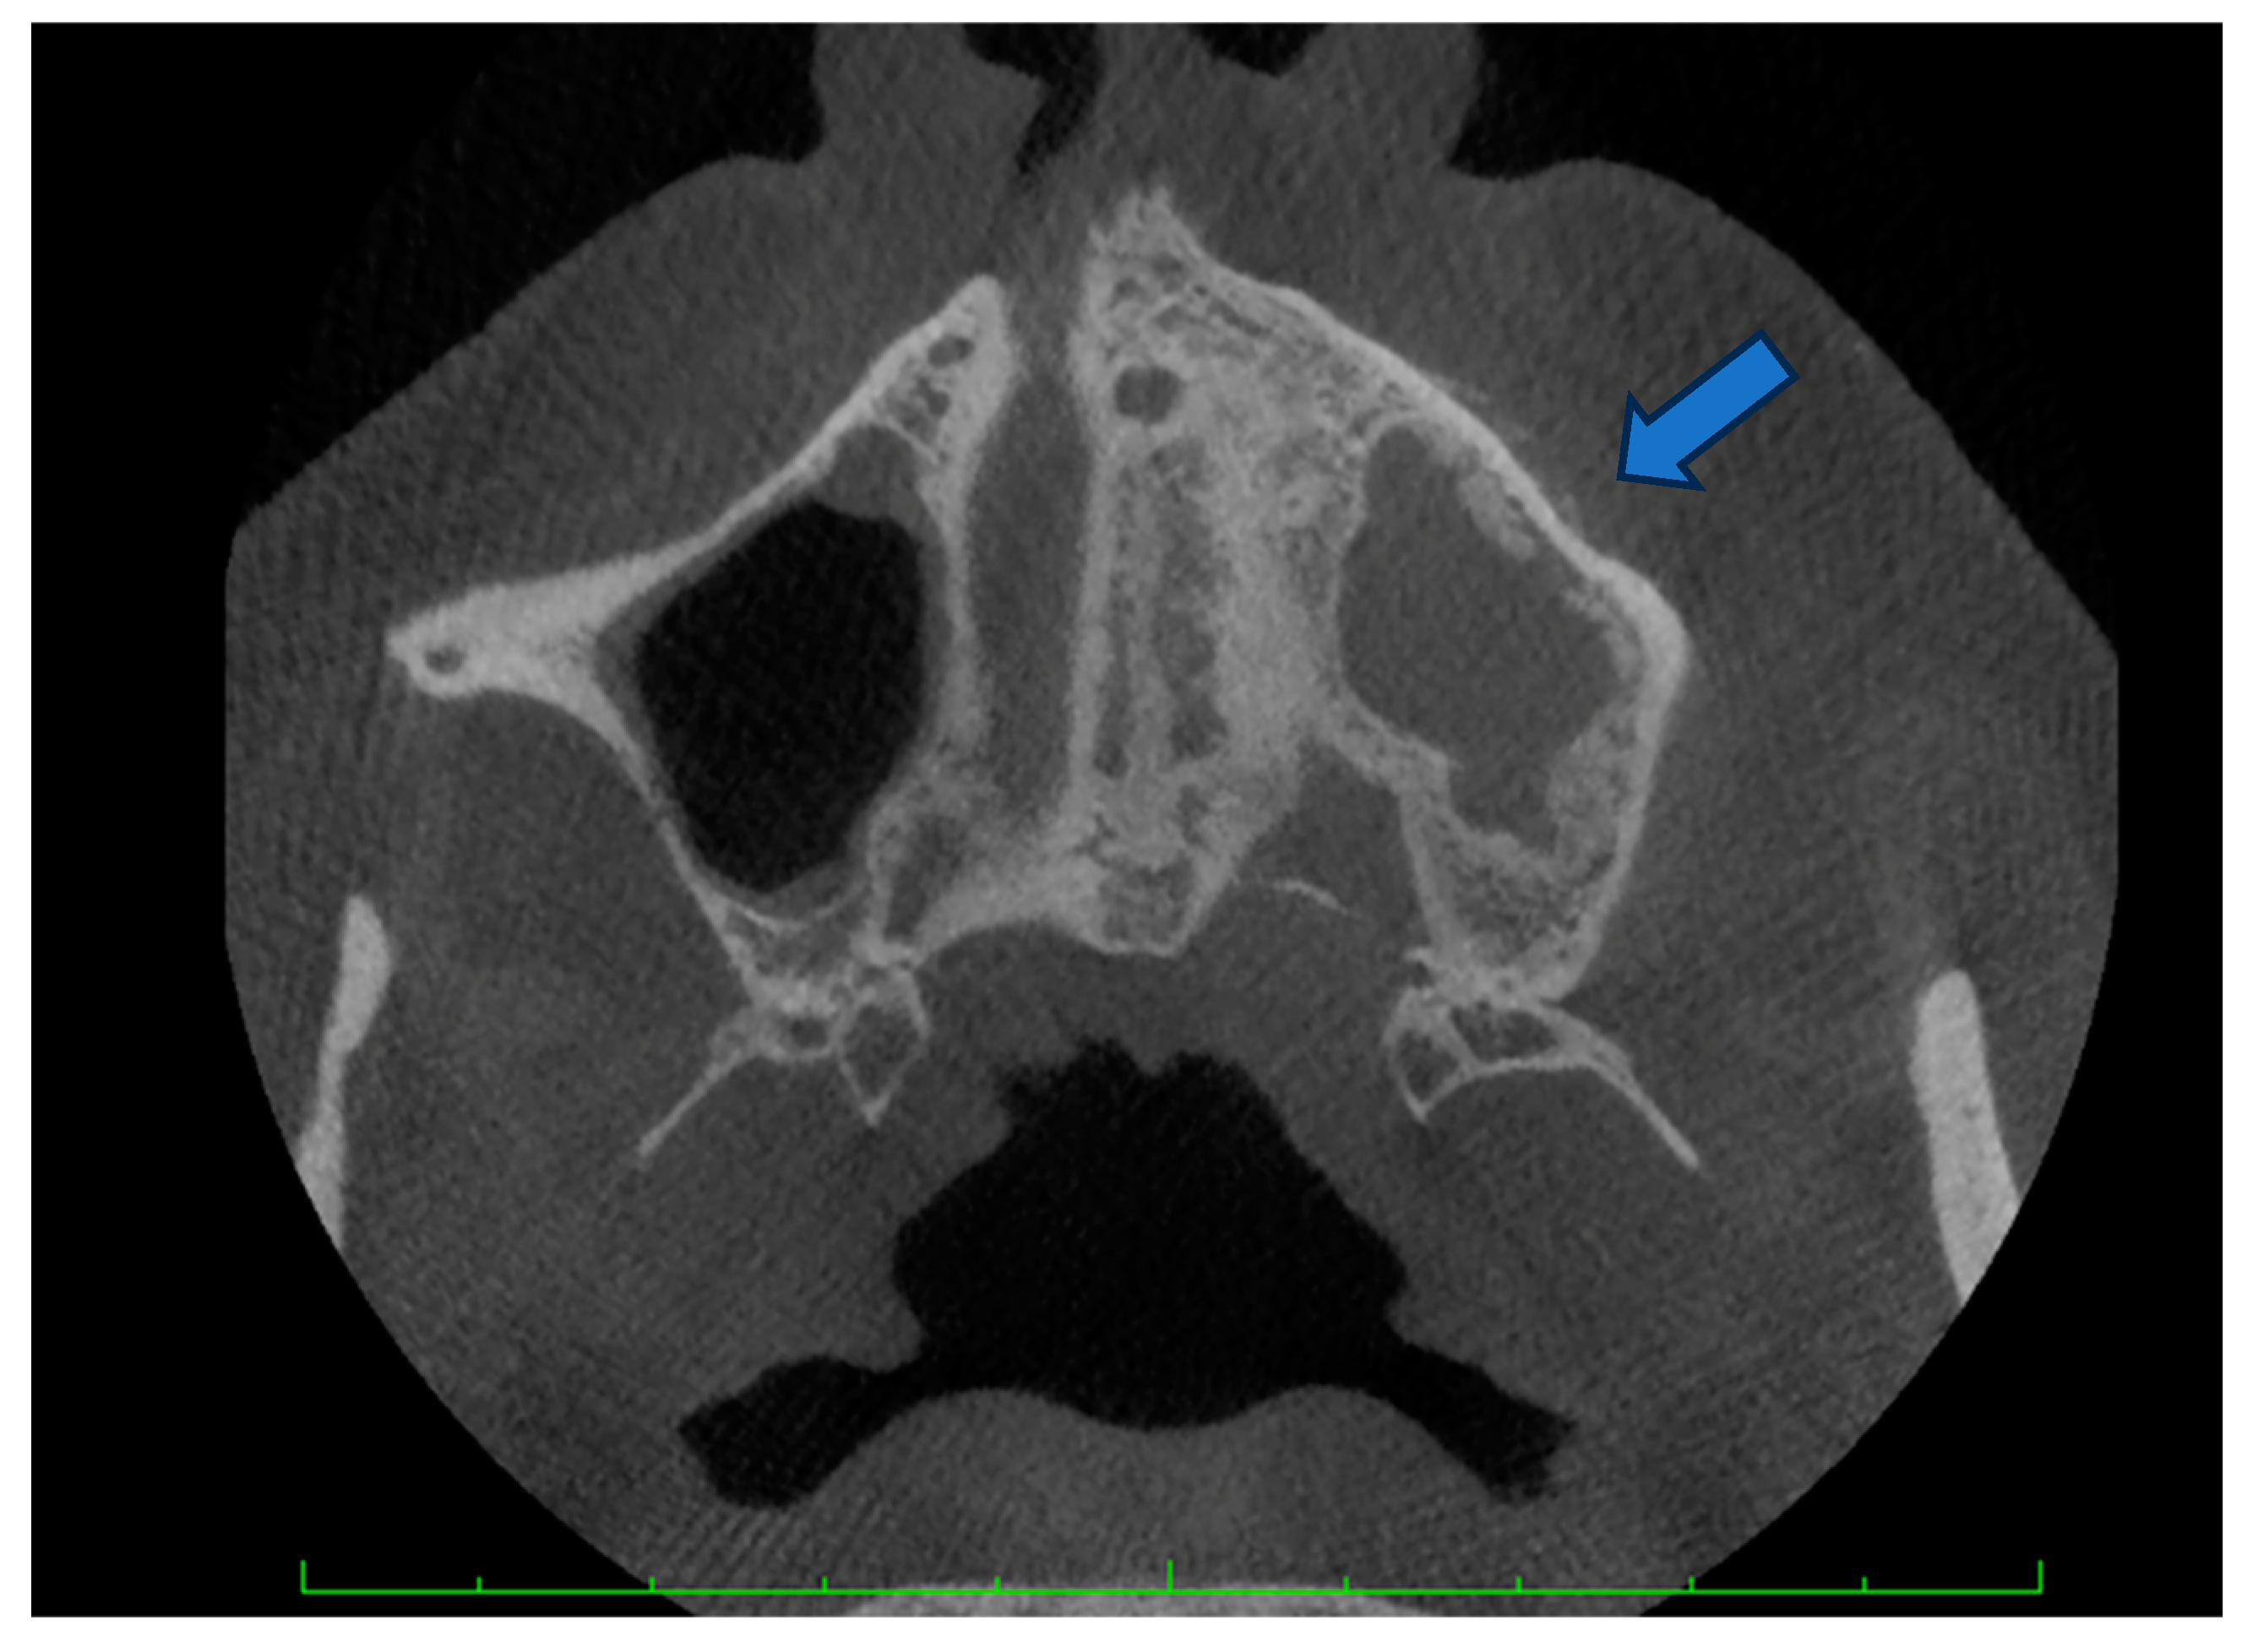

- Osteolysis extending to the inferior border of the mandible or sinus floor